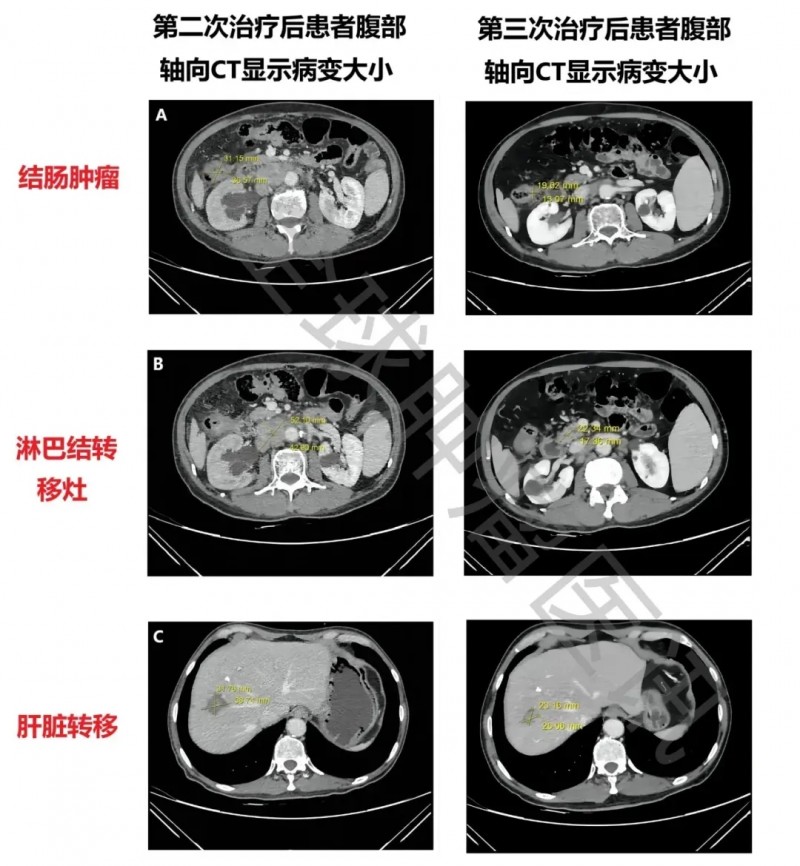

此次联合治疗效果显著:一是所有病灶均明显缩小,结肠肿瘤从3.7cm×3.1cm缩至2.1cm×1.7cm,腹膜后淋巴结转移灶从5.2cm×4.3cm缩至2.3cm×1.4cm,肝脏肿瘤从3.9cm×3.2cm缩至2.9cm×2.3cm(详见下图),最终达部分缓解(PR)(对比第二次治疗,此次肝脏转移灶首次缩小);二是肿瘤标志物显著下降,癌胚抗原(CEA)从30.1μg/L降至4.3μg/L,CA19-9从62.64kU/L降至23.97kU/L。